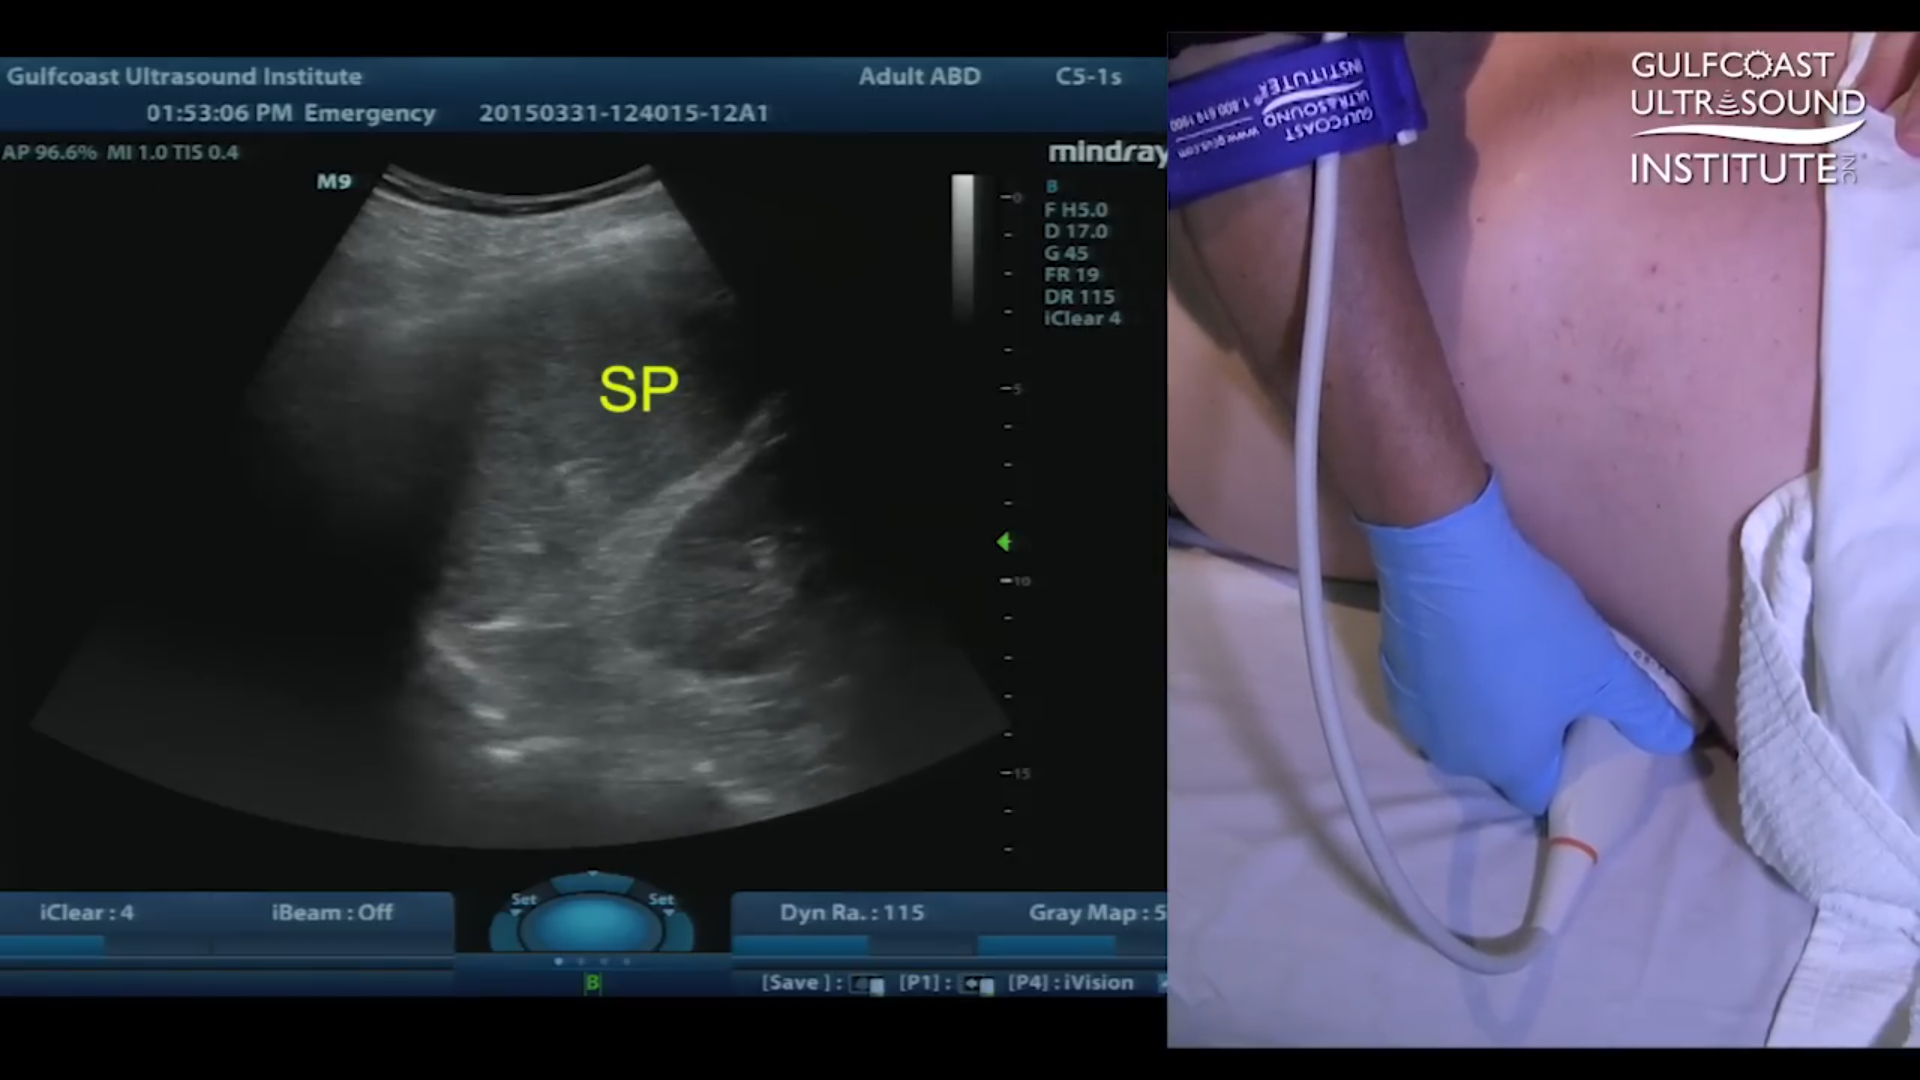

If the traditional right lateral decubitus position isn't feasible for your patient, simply instruct them to remain in the supine position, and here's the secret: have them raise their left arm and position it alongside their head. It may sound like a minor adjustment, but trust us, it can make all the difference in spleen visualization.

By placing their hand on the bed and elevating it towards their head, you're effectively maneuvering the spleen into view. As you scan, pay close attention to the left side of the body, and watch as the kidney comes into frame. Follow its trajectory upwards towards the head, and voila! There, nestled in the sagittal plane, lies the elusive spleen.